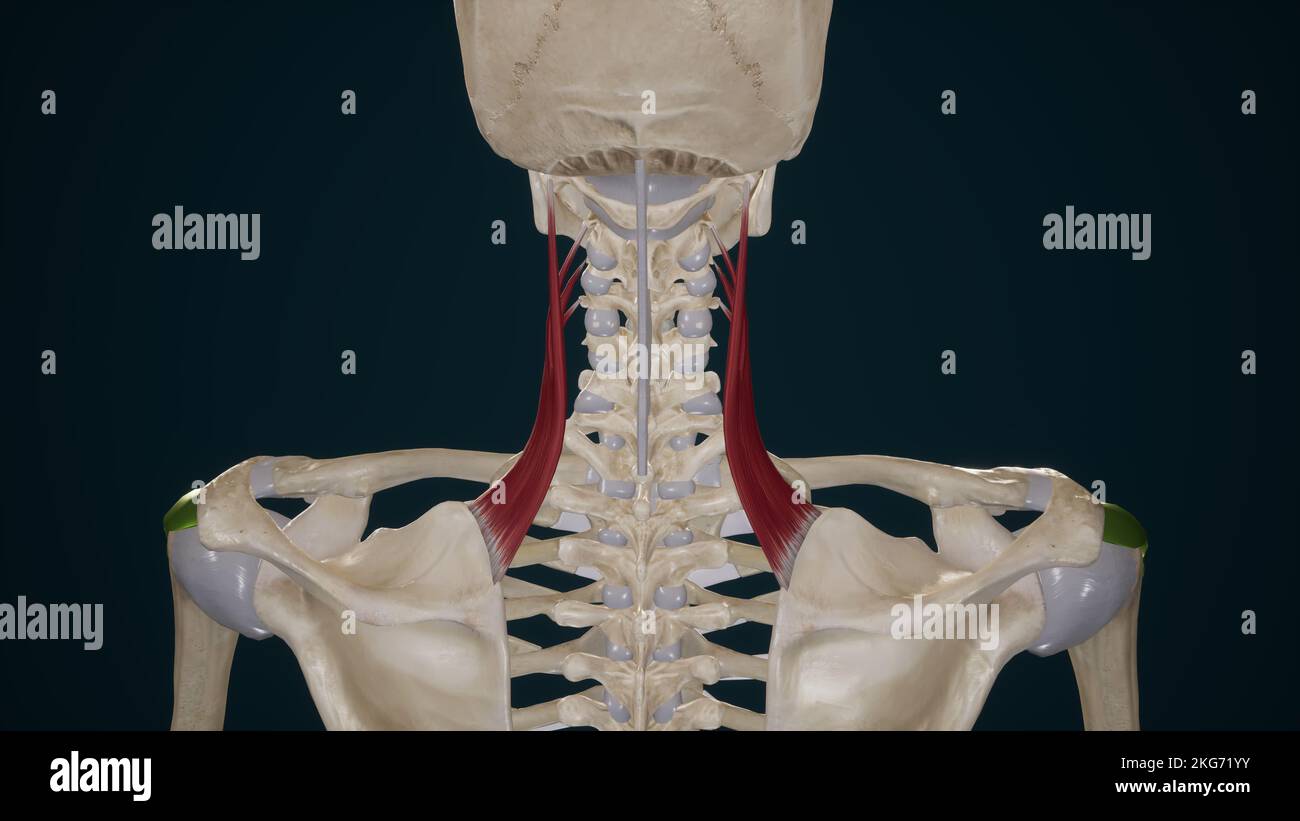

RMJ4C3NM–Questo diagramma di PSM V25 D742 illustra la struttura anatomica delle costole cervicali e il processo trasversale delle vertebre cervicali. È una rappresentazione dettagliata utilizzata nello studio dell'anatomia umana, concentrandosi sulla struttura vertebrale e sullo sviluppo delle costole.